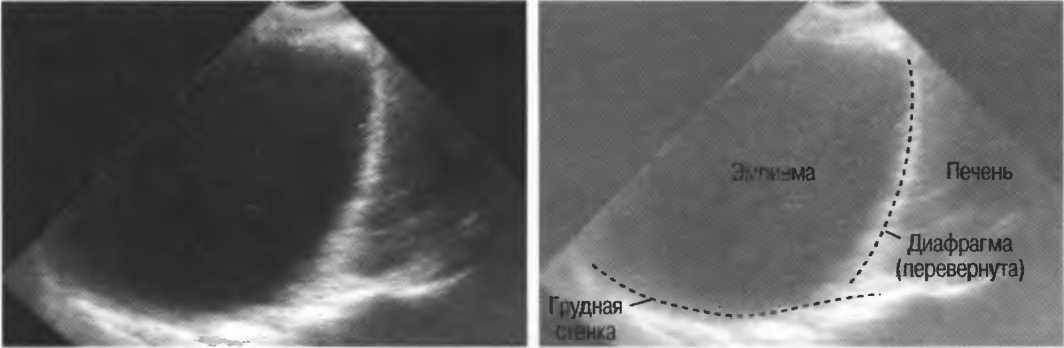

в Найроби, коллективу Найробийского рентгенологического центра;